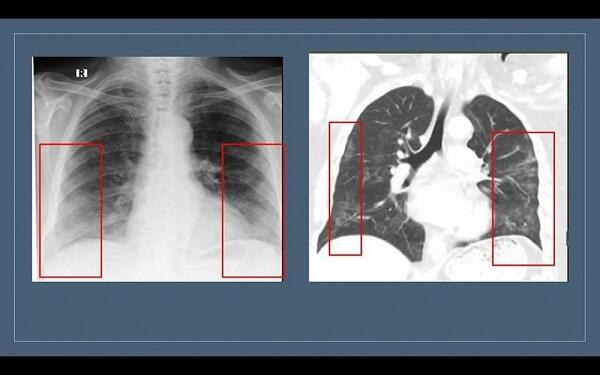

Pandemiya dönəmində insanların sanki kabusuna çevrilmiş bir termin var – “buzlu şüşə” mənzərəsi. Bəzən bunu “buz kristalı”, “buz parçası” kimi də adlandırırlar. Bu görüntü ilk əvvəl adı və səslənməsi ilə insanlarda təlaş, narahatlıq yaradır.

Həkim qeyd edir ki, bəzən normal hallarda da “buzlu şüşə” görüntüsü radioloji görüntülərdə izlənilə bilər: “Məsələn, müayinə zamanı xəstə dərindən nəfəs almazsa və ya müayinə nəfəsvermədə aparılarsa, ağciyərin havalılığının fizioloji ekspirator zəifləməsi səbəbindən bütün ağciyər sahələri homogen olmaqla “buzlu şüşə” görüntüsü verə bilər. Hazırda “buzlu şüşə” görüntüsü koronavirus pnevmoniyasının əsas radiodiaqnostik əlaməti hesab edilir. Bu o deməkdir ki, normalda şəffaf havalı görünən ağciyərdə belə hallarda yarımşəffaf zonalar izlənilir, ağciyər sanki dumanlı görünür. Bu zaman bronx strukturlarının və pulmonar damarların saxlanması ilə ağciyərlərin eksudat və ya transudatla tutulması, interstisial qalınlaşmalar və ağciyər alveollarının hissəvi kollapsı ilə müşahidə olunan görüntü meydana çıxır. Buzlu şüşə xəstəliyin 3-4-cü günlərindən inkişaf etməyə başlayır və xəstə sağaldıqdan hətta bir ay sonra belə qala bilir. Xəstəliyin yüngül və orta ağır dərəcəsini keçirmiş xəstələrdə 2-3 aydan sonra dəyişikliklər tamamilə itir”.

Radioloqun sözlərinə görə, hazırda onlara ən çox verilən sual “buzlu şüşə” görüntüsünün indiyədək mövcud olub-olmaması ilə bağlıdır. Həkim qeyd edir ki, bu, yalnız COVİD-19 xəstələri üçün səciyyəvi deyil, digər xəstəliklərdə də görülə bilər. Lakin bu görüntü pandemiya dönəmində uyğun kliniki-laborator əlamətlərlə izlənilərsə, onda diaqnoz COVİD xəstəliyi kimi dəyərləndirilir.

Qeyd edək ki, “buzlu şüşə” görüntüsü döş qəfəsinin rentgenoqrafiya və kompüter tomoqrafiya (KT) müayinələrində aşkar edilir. Lakin bu məsələdə rentgenoqrafiya müayinəsinin həssaslığı aşağıdır. Ona görə də yoluxmanın ilk 1-4-cü günlərində rentgenoqram 25 faiz hallarda tam normal ola bilər. Bu, pnevmoniyanın olmaması demək deyil. “Buzlu şüşə”nin KT müayinəsində görülməsi daha spesifikdir.